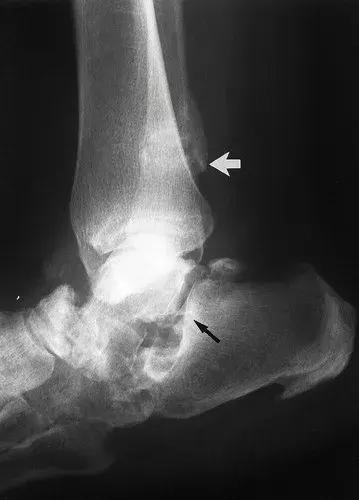

图8:50岁男性,三期梅毒,膝关节的神经性骨关节病。X线片显示胫骨平台受到冲击和破碎(黑色箭头)。在小腿内侧(白色箭头)软组织内可见骨碎片,远离关节。 (来自ACR学习档案,MSK案例234.)